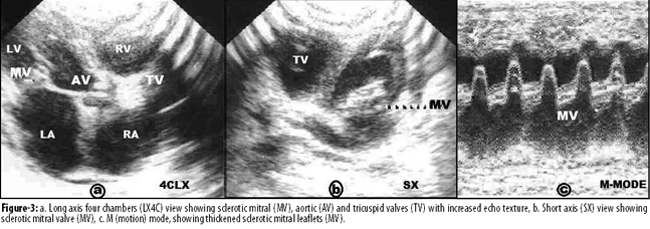

On 2D echocardiography, atherosclerotic dilated ascending aorta with sclerotic aortic valve (Vmax 188/second), thickened sclerotic mitral valve (MVA 1.3 cm2), and aortic and tricuspid valves with increased echo texture were recorded. Right and left atrial and ventricular dilatations and thickened speckled atrial and ventricular septa were recorded. M-mode showed thickened sclerotic mitral leaflets (Figure-3).

We are reporting herein a 6-year-old boy with progeria, who presented with respiratory infection and cardiac failure and was confirmed to have cardiovascular atherosclerotic changes, which included a characteristic systolic (sclerotic) murmur of valvular sclerosis, and signs of congestive cardiac failure. Chest X-rays showed cardiomegaly and the electrocardiogram showed right atrial and ventricular hypertrophy. Echocardiography confirmed dilated atherosclerotic aortic root with septal involvement, and thickened sclerotic aortic, mitral and tricuspid valves, with atrial dilatation and systolic and diastolic ventricular dysfunctions.